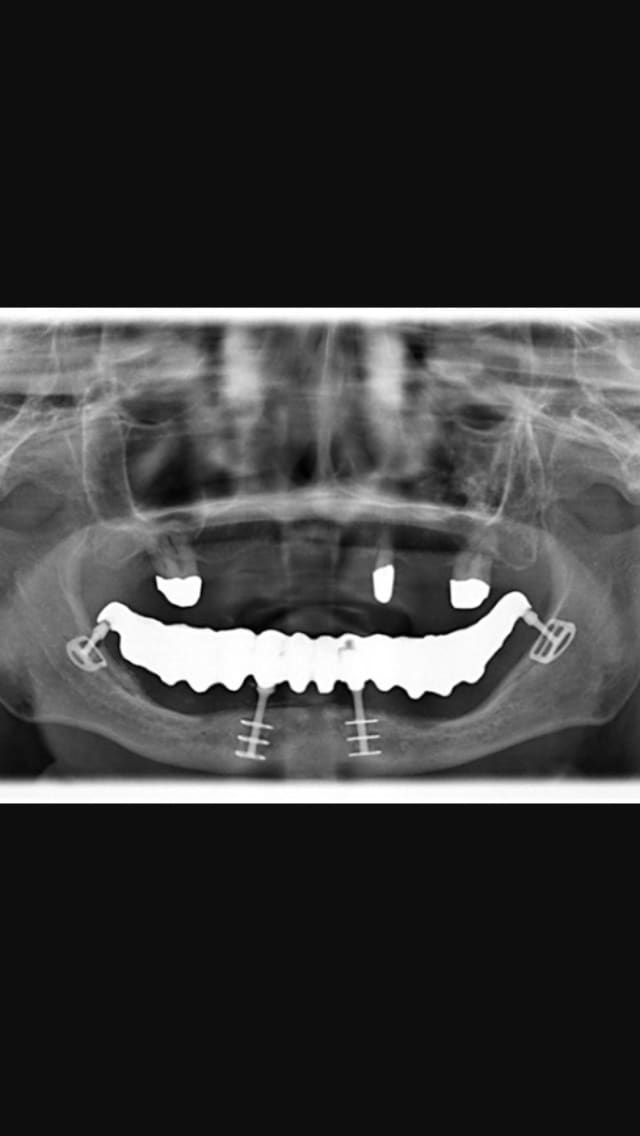

Regarde moi ça 4 Implants et on va jusqu'aux 7 voir jusqu'aux 8 sans problùme 😊

Img 1219 gvmsjs - Eugenol